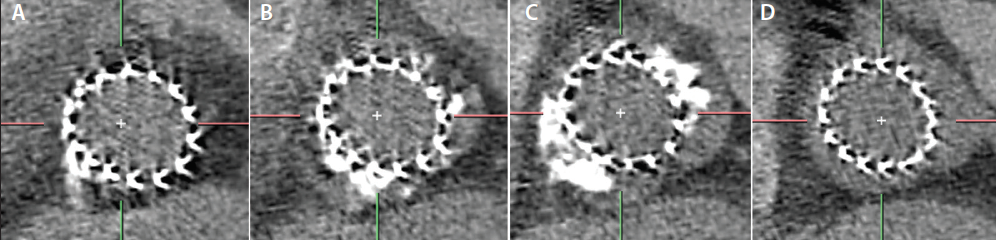

There is no consensus on the appropriate methodology for BAV sizing. Various techniques have been proposed: annulus-based sizing, supra-annular tracing, measuring the intercommissural distance (ICD), and balloon sizing (Figure 2). In the BAVARD registry,9 we retrospectively captured the sizing ratios utilized in contemporary practice and proposed both the dimension of the aortic annulus and the ICD, considering the lower value as the reference for prosthesis size choice. Both the annulus and ICD (4 mm above the annulus) are reproducible measurements, but supra-annular tracing is prone to inter- and intraobserver differences. According to the BAVARD registry, the aortic annulus dimensions are relevant in almost 90% of cases. The ICD should be used in the remaining patients with tapered configurations. In a tapered configuration, the ICD provides a smaller dimension than the aortic annulus, and it is used for sizing in order to decrease the risk of aortic root injury generated by an aggressive oversizing. When using the annular mean perimeter-derived diameter as the reference, the average oversizing ratio was 3% to 5%, in contrast to a 1:1 ratio when utilizing the ICD.

Finally, balloon sizing may be used in borderline cases, but MDCT-based sizing remains the gold standard. Balloon sizing aims to identify the location of a balloon waist, evaluate sealing, and, in cases with a high risk of coronary obstruction, evaluate sealing and the movements of calcified nodules toward the coronary ostia. A balloon is sized according to the aortic annulus and the supra-annular dimensions and aortography is performed during full inflation. Small sizing ratio differences exist between self-expanding, balloon-expandable, and mechanically expanded platforms, and these were also captured in the BAVARD registry.